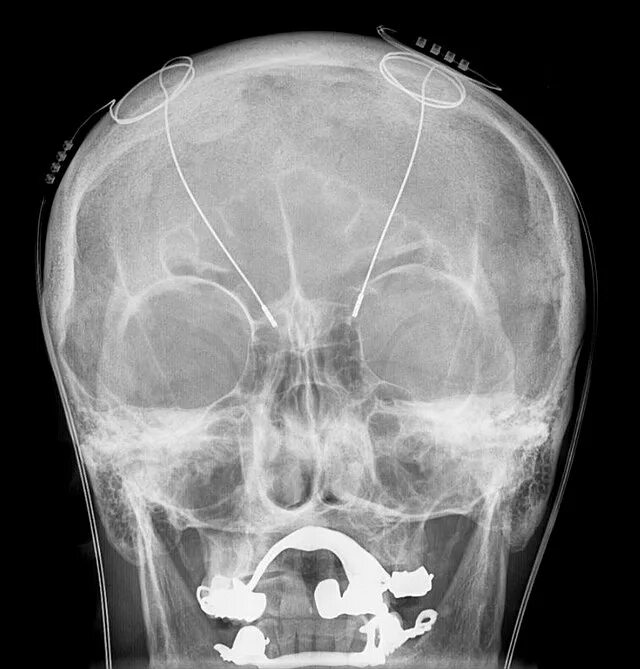

Снимок черепа в прямой проекции